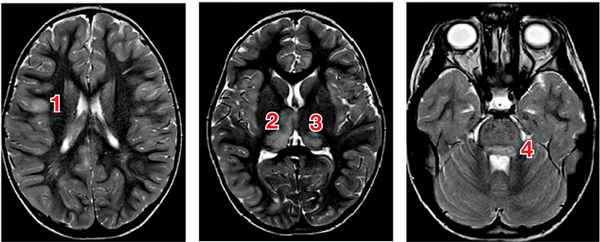

При оценке прогностической ценности структурной МРТ и данных DTI и МРС у пациентов с энцефалитом типа LGI1 (leucin-rich glioma-inactivated 1 protein) было установлено, что в остром периоде на структурной МРТ изменений где-либо, кроме височных долей, не выявлено; по данным DTI регистрировались широко распространенные изменения белого вещества полушарий и мозжечка со снижением по данным МРС уровня глутамина и глутамата [18]. Прогностически значимыми, с точки зрения исходов, оцениваемых по шкале Рэнкина и по шкале когнитивного дефицита Адденбрука, оказались объем сохранного серого вещества и степень дезинтеграции трактов в белом веществе. При рабическом энцефалите, ВИЧ-ассоциированной лейкоэнцефалопатии, японском энцефалите и энцефалите, вызванном вирусом Эпштейна–Барр, также сообщается о значительно более широком спектре поражения головного мозга, выявляемого с помощью DTI, по сравнению с таковым по данным структурной МРТ [19–22]. Пример изменений, выявляемых с помощью структурной МРТ при энцефалитах у детей, представлен на рис. 1.

Рис. 1. МРТ головного мозга пациентки Х., 4 года: энцефалит цитомегаловирусной этиологии, острый период заболевания

Примечание. На МРТ в последовательностях Т2 и FLAIR выявляются очаги воспаления в коре (1), таламусах (2, 3) и стволе мозга (4) (собственные данные).

При стволовом энцефалите, обусловленном энтеровирусом EV71, регистрация билатеральных симметричных или унилатеральных гиперинтенсивных Т1 и Т2 очагов, расположенных в задней части ствола, сочетавшихся с очагами в шейном отделе спинного мозга, коррелировала с неблагоприятным прогнозом — смертность у детей с подобным паттерном была достоверно выше, чем у пациентов, у которых регистрировались неинтенсивные одиночные очаги в задней части ствола, не сочетавшиеся с поражением спинного мозга [23].

При проведении структурной МРТ у детей с клещевым энцефалитом описывается широкий спектр изменений с частым поражением таламуса [24–27], хотя прогностического значения при данной этиологии заболевания процедура не имела. В таких случаях рекомендуется проведение МР-спектроскопии [28]. С другой стороны, в исследованиях с участием 111 и 656 пациентов сообщается о достоверной корреляции неблагоприятных исходов клещевого энцефалита с данными структурной МРТ (площадью и расположением очагов) [29, 30].